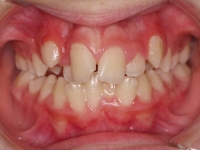

El paciente A.J. de 11 años, acude a nuestra consulta con apiñamiento maxilar importante. El canino lateral (12) está en mordida cruzada. Presenta una Clase II molar y canina, y la línea media está desviada. Se realizó un tratamiento con brackets autoligables metálicos de smartclip 022. La duración del tratamiento fue de 22 meses.

El paciente actualmente ha terminado el tratamiento con brackets y lleva una contención fija de 2-2 en maxilar y 3-3 en mandibular; para complementar también lleva una férula ESSIX durante la noche.

INICIO FINAL